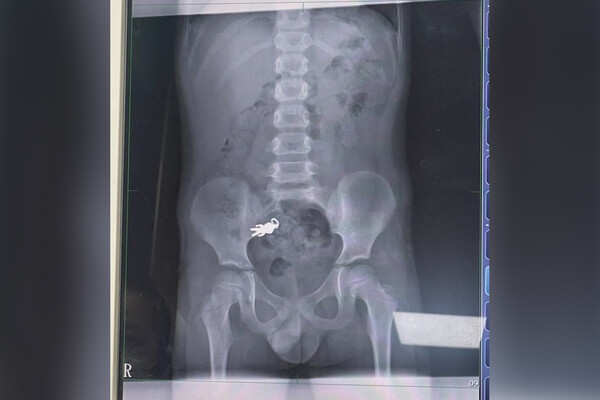

В кишечнике семилетнего мальчика нашли фигурку Ультрамена

На Тайване семилетний мальчик случайно проглотил металлический брелок с фигуркой Ультрамена (герой Вселенной комиксов DC — «Газета.Ru»). Об этом сообщает издание Must Share News.

По информации издания, инцидент произошел, когда ребенок смотрел телевизор. Мальчик ел печенье и крутил в руках брелок, периодически засовывая его в рот. В какой-то момент ребенок от неожиданности проглотил предмет.

Родители, узнав о случившемся, привезли сына в городскую больницу. Там пациенту сделали рентген, который подтвердил слова несовершеннолетнего. К моменту визита медицинского учреждения Ультрамен уже переместился в тонкую кишку. После осмотра медики сделали вывод, что брелок должен выйти из кишечника естественным способом, и пациента отправили домой. Позже родители подтвердили, что удалось обойтись без оперативного вмешательства.